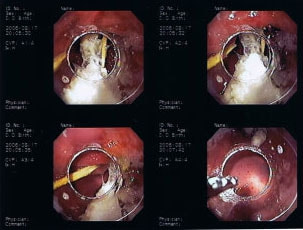

9歳 チワワ 4.8kg

主訴:2日前の夜に桃の種を飲み込んだとのこと。元気・食欲に問題はなく、嘔吐などの消化器症状もみられなかった。誤飲した当日に他院にて催吐処置を試みたが、吐き戻さなかったとのこと。

単純レントゲン検査:明らかな異常所見なし

消化管バリウム造影レントゲン検査:胃内にて異物の存在を疑う異常所見を認めた。

内視鏡検査:内視鏡下にて、バスケット鉗子を用いて胃内異物を摘出。

異物内容:桃の種 (約4cm大 写真上)、とうもろこしの芯 (約2.5cm大 写真下)

本症例は、床に落としてしまった桃の種を誤飲していました。動物の体格に対して異物が非常に大きく、開腹手術となる可能性があった症例でした。また、桃の種と一緒に出てきたとうもろこしの芯は、日々のおやつとして与えていたものということでした。とうもろこしの芯は非常に硬く、小さく切って与えても消化されず、長期間胃内に残ってしまうことや腸閉塞の原因となる為、注意が必要です。